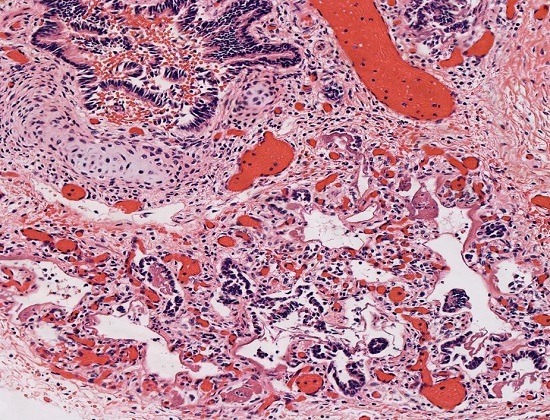

Lung hypoplasia is defined as the ratio of lung weight to body weight. The ratio is 0.012 for newborns at 28 weeks’ gestation or more and 0.015 for those of lower gestational age.4 In our case, taking into consideration the baby’s weight of 2670 g (normal for gestational age: 2501-2750 g)5 the ratio is 0.01. Microscopic examination of the lungs showed irregular tubules lined by pseudostratified to simple columnar epithelium with rare alveolar sacs consistent with the late pseudoglandular (pre-acinar) stage of development, hyaline membranes, and abundant septal fibrosis. The presence of immature cartilage formation around bronchial-like structures with appropriate accompanying vessels and normally-formed lymphatics were noted (Figures 2 and 3).

These findings are consistent with the diagnosis of congenital acinar dysplasia. Additional autopsy findings were recent intraventricular hemorrhage and a small chest circumference of 28.8 cm (normal for gestational age: 33 ± 2.3 cm).5 A pertinent negative finding was that of no cardiac malformations.